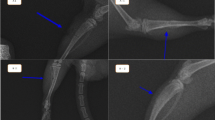

Rats were anesthetized with a mixture of 0.4 mL of 10 % ketamine (114 mg/kg), 0.2 mL of 2 % xylazine (11.4 mg/kg), and 0.1 mL of fentanyl citrate (1.4 mg/kg) by intramuscular injection. Rats were then placed securely on the operating table in the ventral decubitus position. An incision was first made through the skin and subcutaneous tissue in the anterolateral region of the right thigh. The fascia was then opened, and the femur was accessed at the space between the rectus femoris and the vastus lateralis muscles. The middle third of the femoral shaft was exposed and a straight titanium plate (22 mm × 3 mm × 0.5 mm) with central space and four holes (Synthes Ind., Rio Claro, Brazil) was fixed to it with 1.5- and 1.7-mm stardrive cortex screws, according to the femur diameter. The bone was sectioned using an oscillating saw (Implantek Lase, DMC Equipment, São Carlos, Brazil) at 500–800 rpm, with continuous irrigation with saline solution to the site. An experimental model of complete bone fracture was created by removing a 2-mm fragment from the middle third of the femoral shaft (Fig. 1). A precision pachymeter was used to measure the size of the gap to ensure the distance between the fragments. After fracture creation, the muscles were approximated and the skin was closed with continuous sutures. Enrofloxacin (30 drops) was added to the rats’ drinking water daily. Analgesics were not administered and splint elements were not used.

With regard to microscopic parameters (Fig. 3), better results were found for group A than for group B (Fig. 4a, b). The fracture sites from all rats sacrificed at day 8 (subgroups A1 and B1) showed similar degrees of inflammatory infiltration, whereas only the rats of subgroup A2 (on day 13) showed a significantly lowered inflammatory infiltration response (p = 0.015), as shown in Fig. 5a, b. This lower degree of inflammation was maintained at day 18 (subgroup A3; p = 0.028). LLLT rats in subgroups A1, A2, and A3 showed an emergence of trabecular bone formation over time, with significant differences among the three subgroups measured (p < 0.01 for all 3 days). In contrast, no trabecular matrix formation was observed for any of the control rats (subgroups B1, B2, or B3). Periosteal formation was not seen in any of the rats after 8 days of healing (subgroup A1 and B1), but a high percentage of animals with periosteal formation were found by day 13 in the LLLT group (subgroup A2) as compared with control rats at the same time point (subgroup B2; p = 0.001). This increased periosteal response at day 13 was maintained to day 18 for LLLT rats (subgroup A3) whereas control rats at day 18 had only just started to show periosteal differences (subgroup B3 p = 0.005). With regard to bone formation, significant differences were measured among the groups at each time point, with better results identified for LLLT rats (subgroups A1, A2, and A3) as compared with their respective control counterparts (subgroups B1, B2, and B3; p < 0.001 for all periods).

When creating a clinical bone fracture model, it is crucial to produce a gap that prevents contact between the bone fragments, as contact might provide a more favorable environment for the union process and facilitate bone growth. Besides this, bone defects of small diameters are not sufficiently reliable to demonstrate the efficacy of lasers as biomodulatory therapies for bone repair [1, 17]. In our model, the stability provided by the plate allowed ambulation and weight bearing [18].